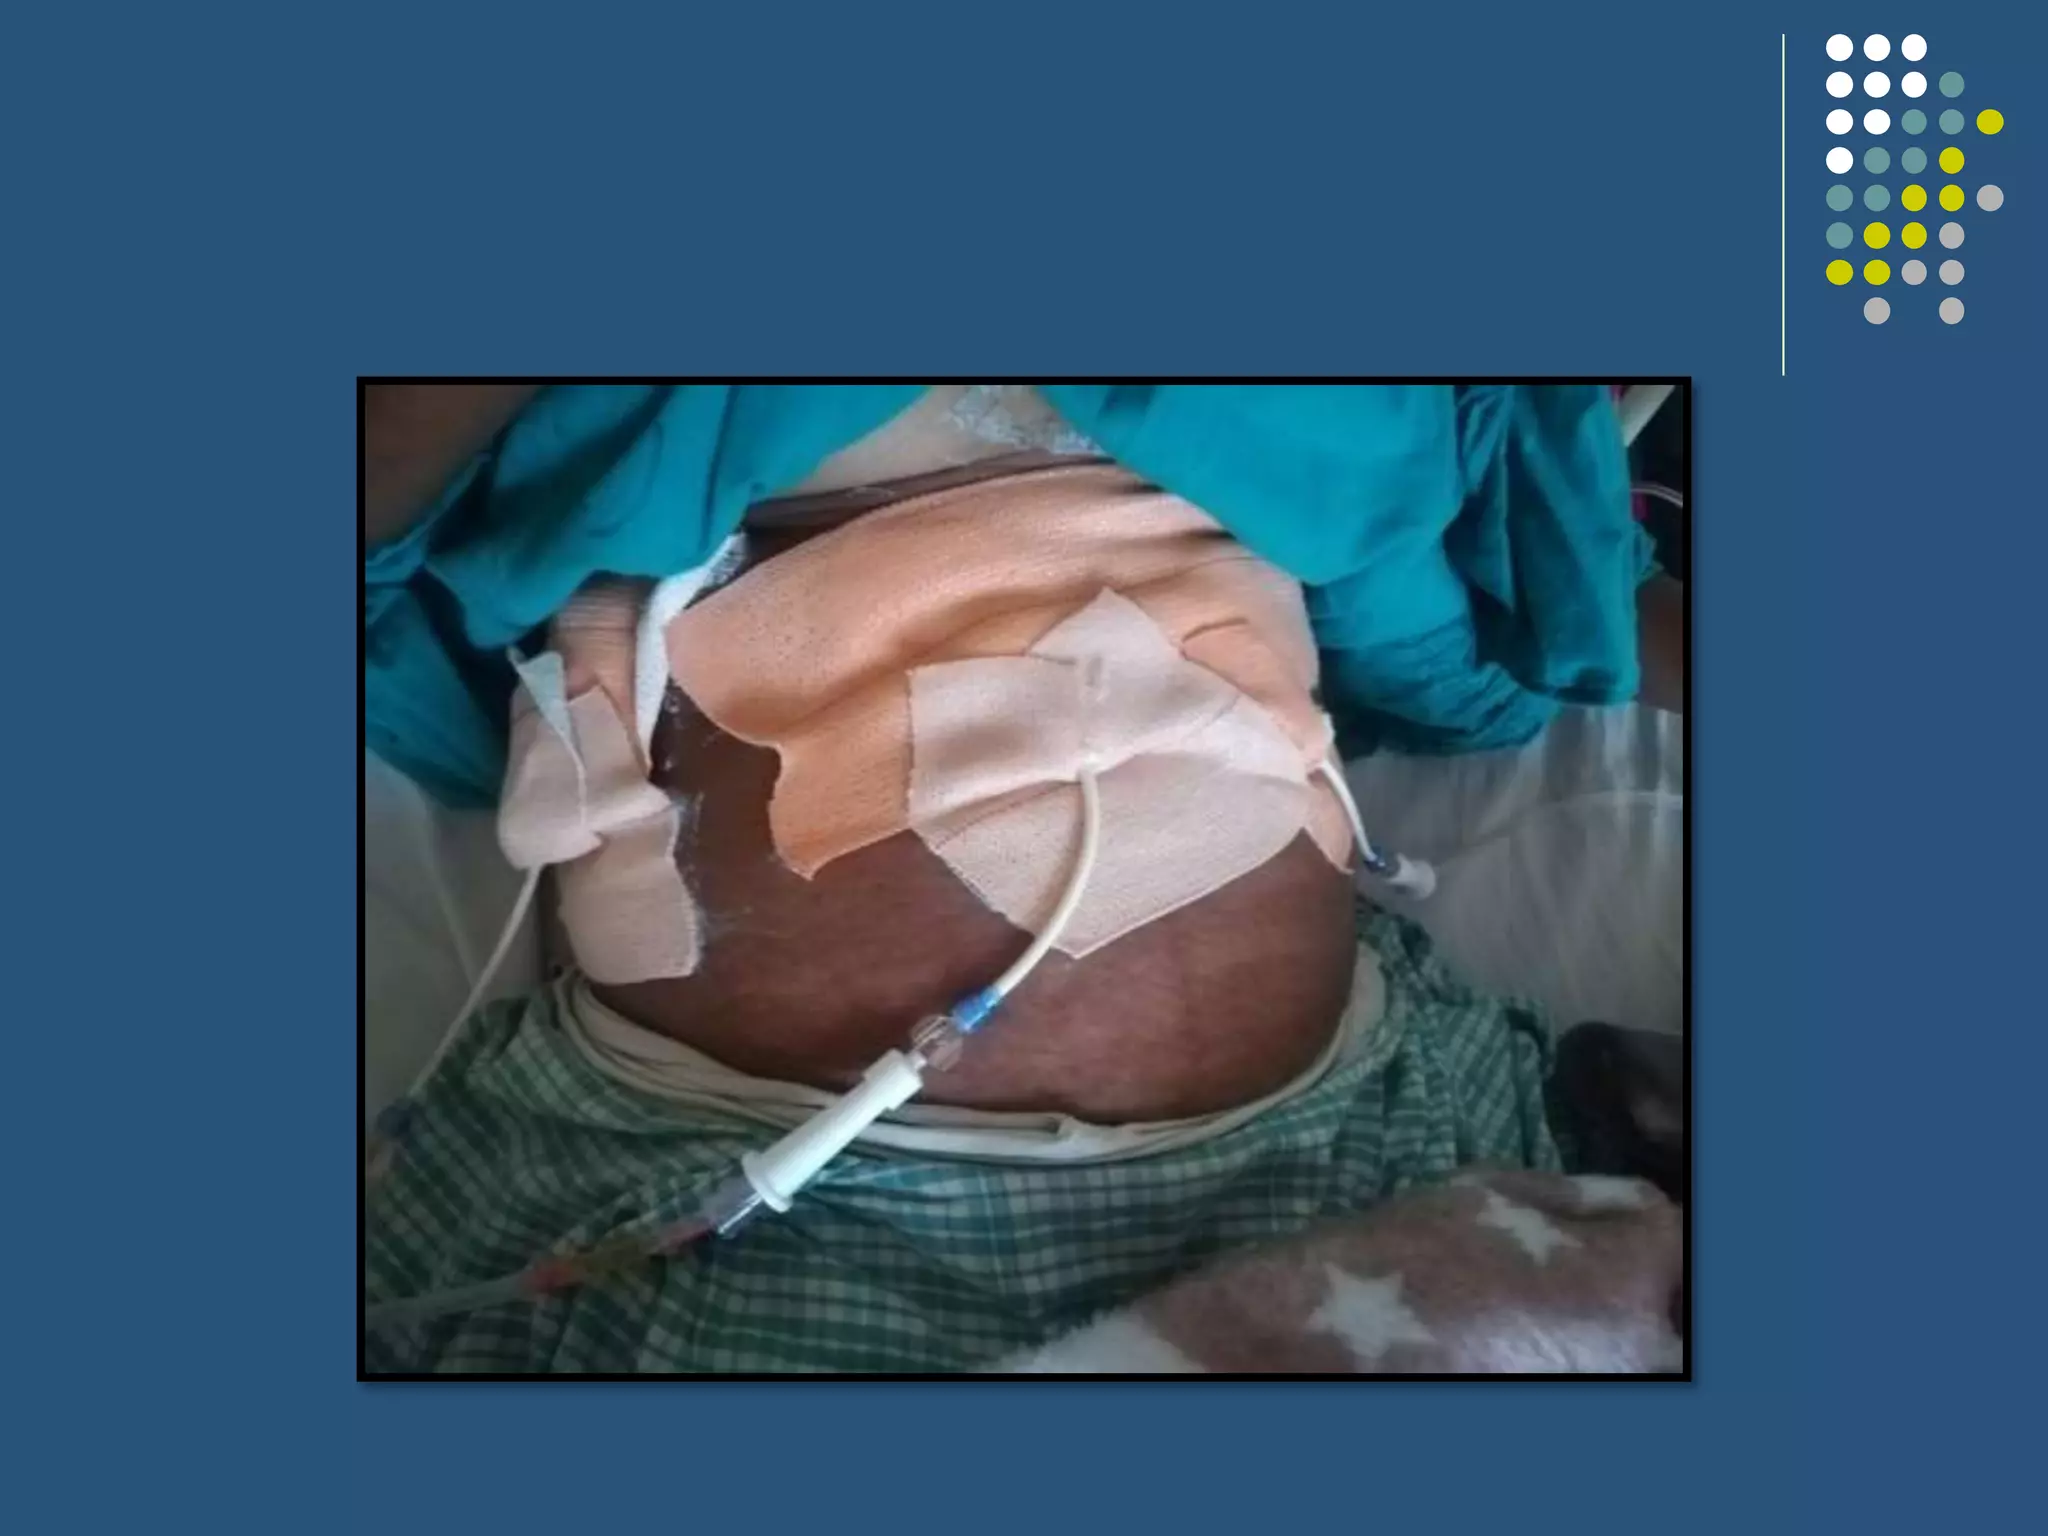

This case presentation describes a 60-year-old female patient who presented with 1 month of abdominal pain and 7 days of fever. Imaging revealed multiple rim-enhancing lesions in the liver consistent with pyogenic liver abscesses. The patient was diagnosed with pyogenic liver abscess and treated with intravenous antibiotics and drainage of the abscesses. Liver abscesses can have various causes but are often related to biliary tract or gastrointestinal infections. Diagnosis involves imaging and drainage or aspiration of pus is usually needed along with broad-spectrum intravenous antibiotics administered for at least 2 weeks.